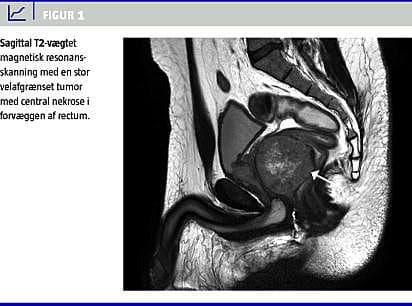

En 39-årig mand blev henvist fra egen læge til udredning i rectumpakken, da han havde defækationssmerter, seks måneders tiltagende frisk blødning per rectum og en stor rektal tumor, der var fundet ved digital eksploration. På kirurgisk afdeling fandt man ved fleksibel sigmoideoskopi en rectumtumor, der blødte ved berøring og biopsitagning. Biopsien viste nekrotisk materiale. Magnetisk resonans (MR)-skanning af det lille bækken viste 5,5 cm oppe på forvæggen af rectum en velafgrænset ekstraluminal tumor på 7 cm i diameter. Tumoren var hyperintens på T2-vægtede sekvenser (Figur 1 ) og således ikke karakteristisk for det hypointense adenokarcinom, hvorfor GIST blev anført som differentialdiagnose. En transrektal ultralydskanning viste en hyperekkoisk tumor med central nekrose. Computertomografi (CT) af thorax og abdomen med intravenøst kontraststof viste ingen metastaser. Der blev ikke påvist patologisk udseende lymfeknuder ved hverken transrektal ultralydskanning, MR-skanning eller CT. Fornyet endoskopisk biopsi viste en tencellet tumor med positiv immunhistokemisk farvning for CD117 (kit-tyrosinkinase) og CD34, hvilket er diagnostisk for GIST. Der var højst en mitose pr. ti high power field (HPF). Patienten blev overflyttet til Odense Universitetshospital, hvor han undergik komplet kirurgisk resektion med frie resektionsrande og fik udført permanent kolostomi. I præparatet var der to mitoser pr. 50 HPF. En mutationanalyse viste mutation i kit-exon 11. Tumoren blev klassificeret som intermediær risiko. Der blev ikke givet nogen efterbehandling. Der blev planlagt opfølgende kontrol med CT af thorax og abdomen hvert halve år.